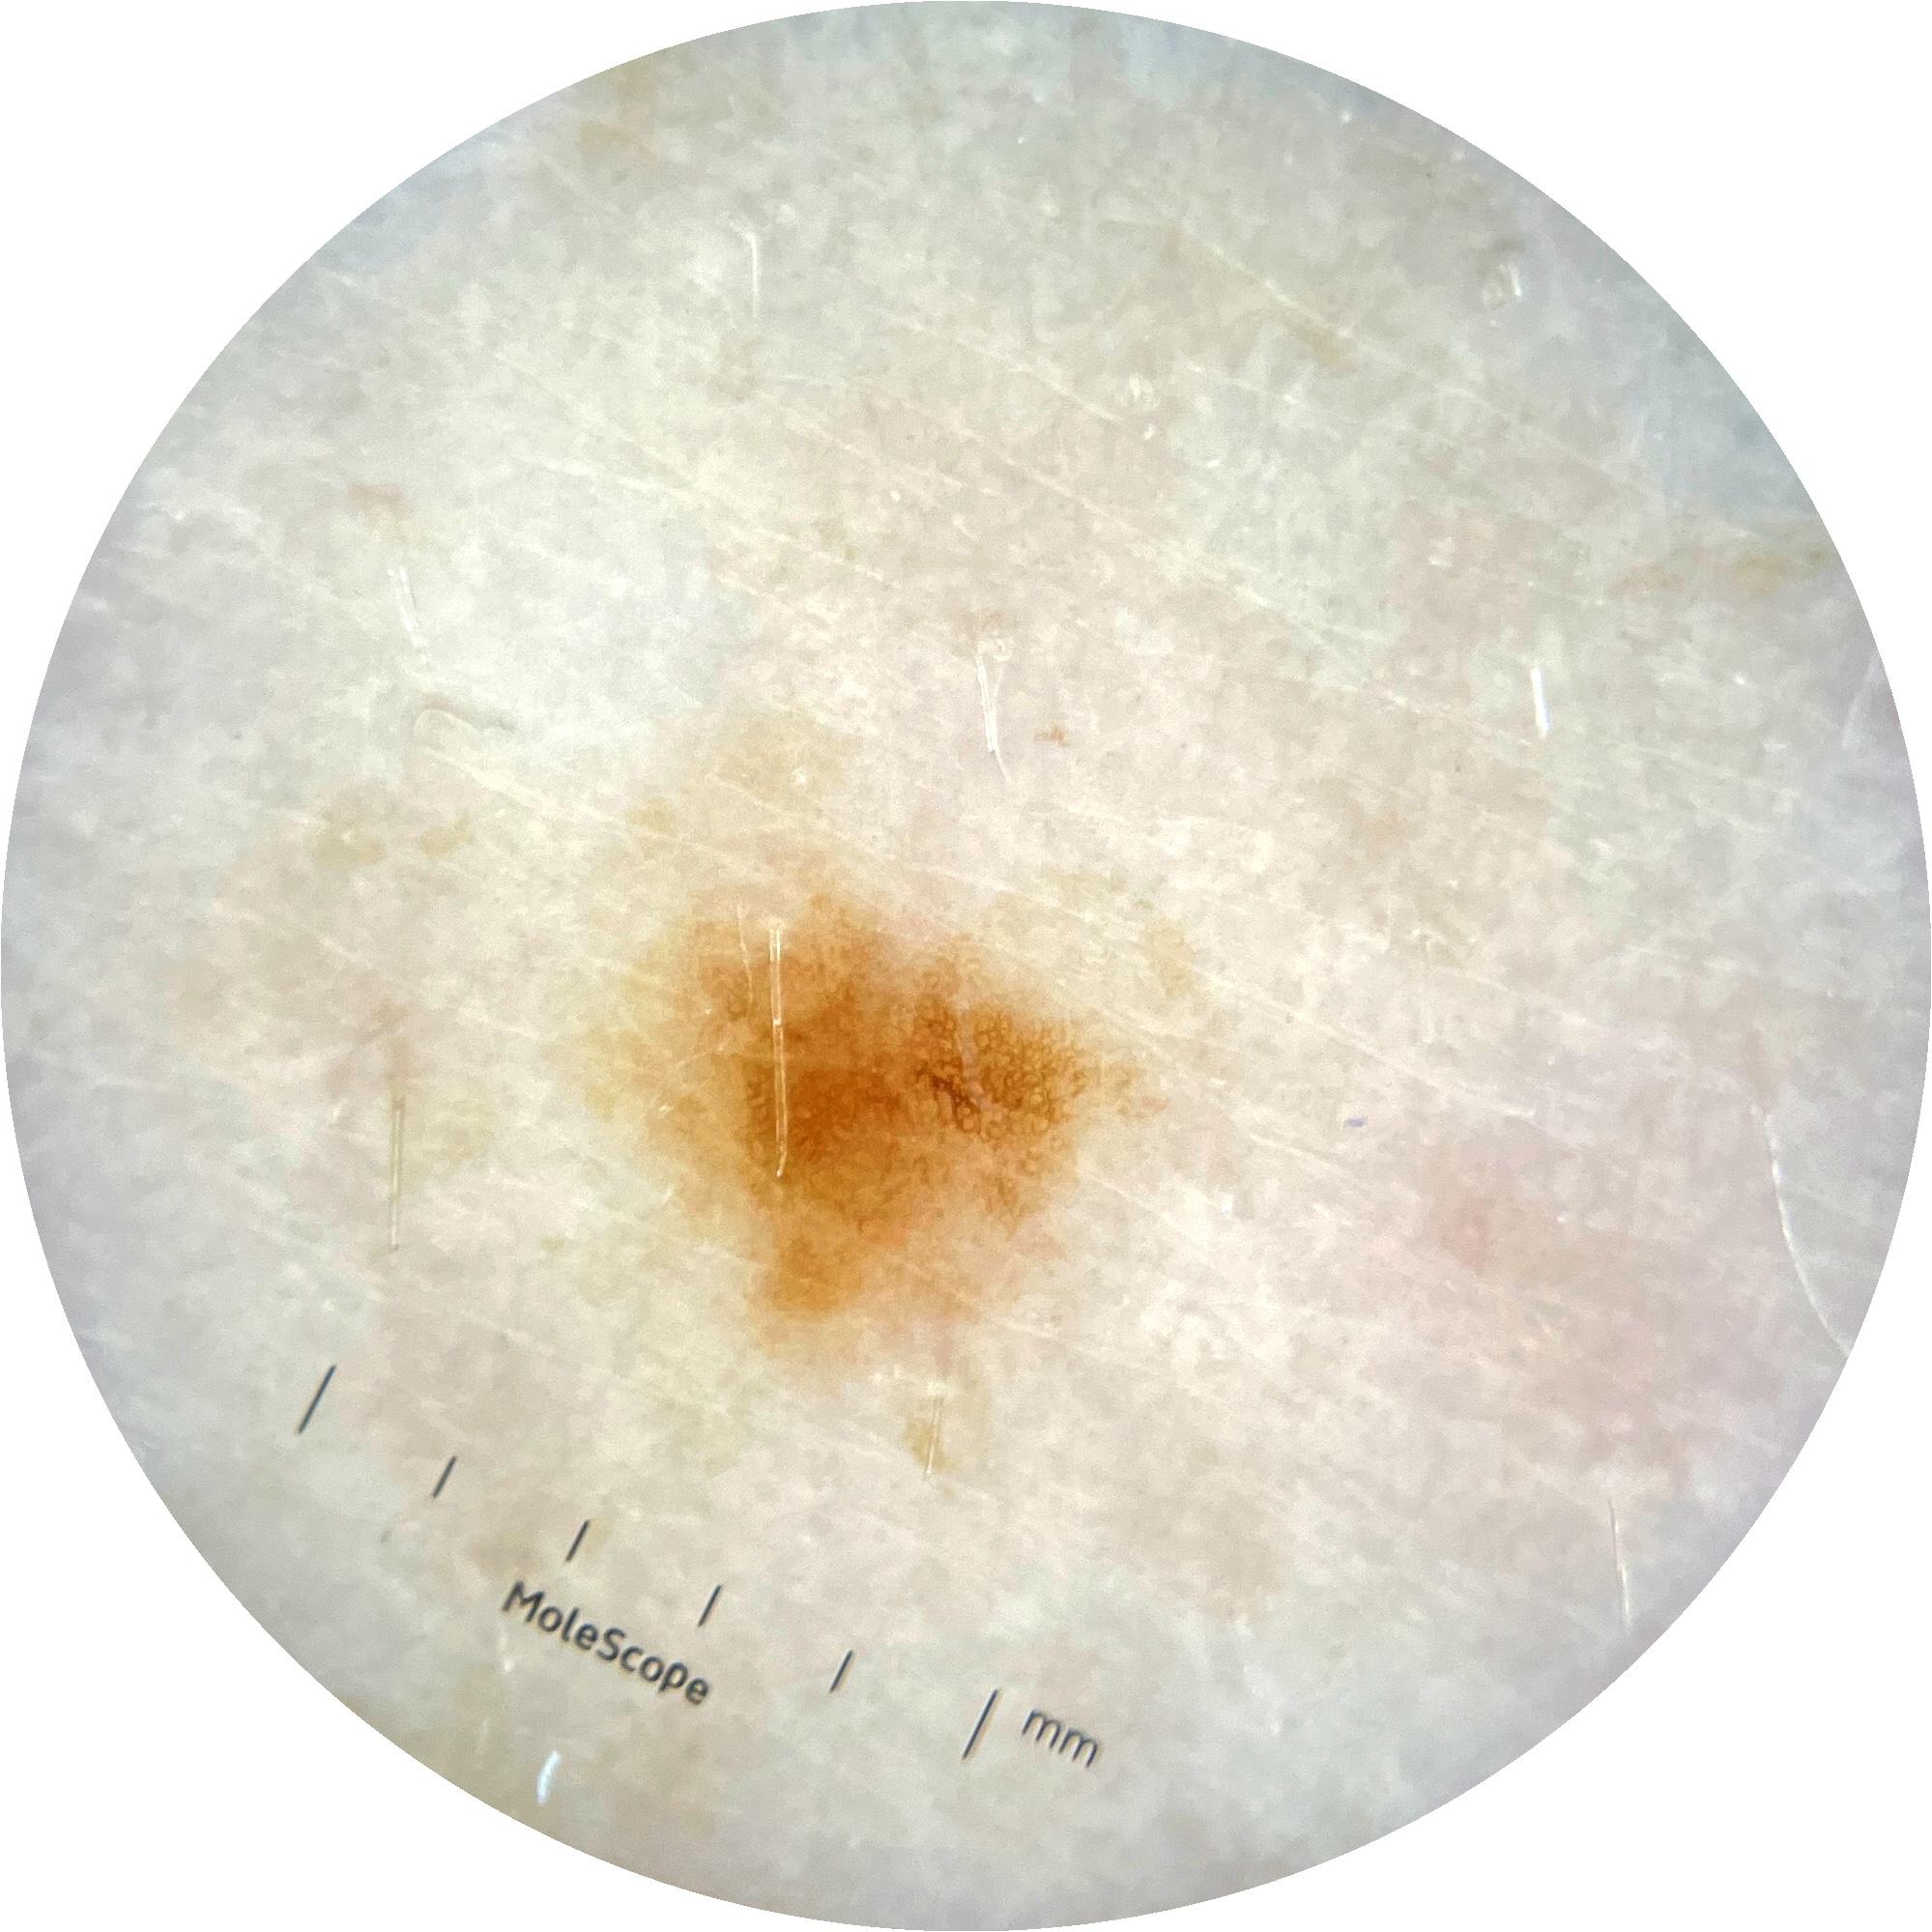

ISIC_9785574

2003 x 2003

Clinical

Field Value

acquisition_day 148

age_approx 45

anatom_site_1 Head and neck

anatom_site_general head/neck

diagnosis_1 Benign

diagnosis_confirm_type single image expert consensus

image_type dermoscopic